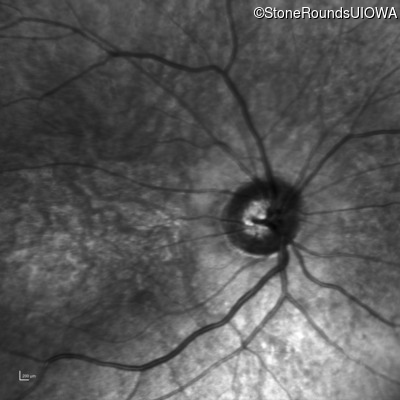

Infrared Fundus Photograph - Right - 10/200

Exemplar